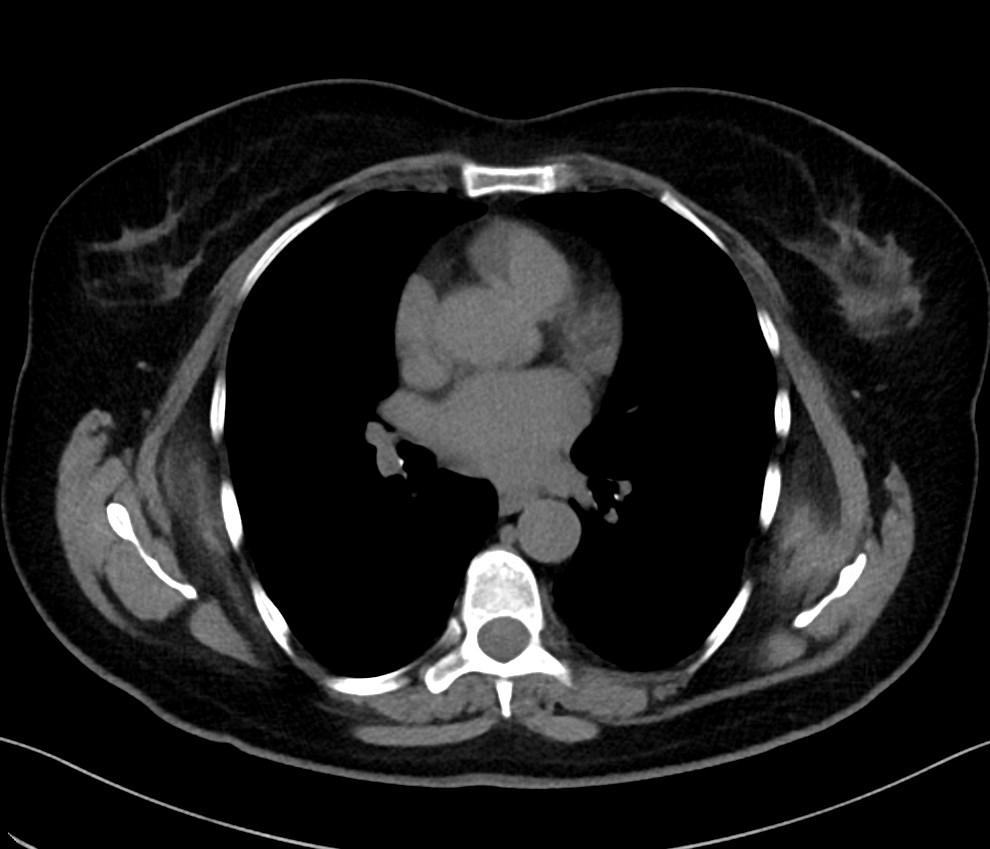

CT images showed bilateral poorly defined soft-tissue mass with attenuation similar to that of the adjacent skeletal muscle. They are located in the infrascapular region suggestive of elastofibroma dorsi lesions.

Elastofibroma dorsi is a benign soft-tissue tumor with a characteristic location and imaging appearance.